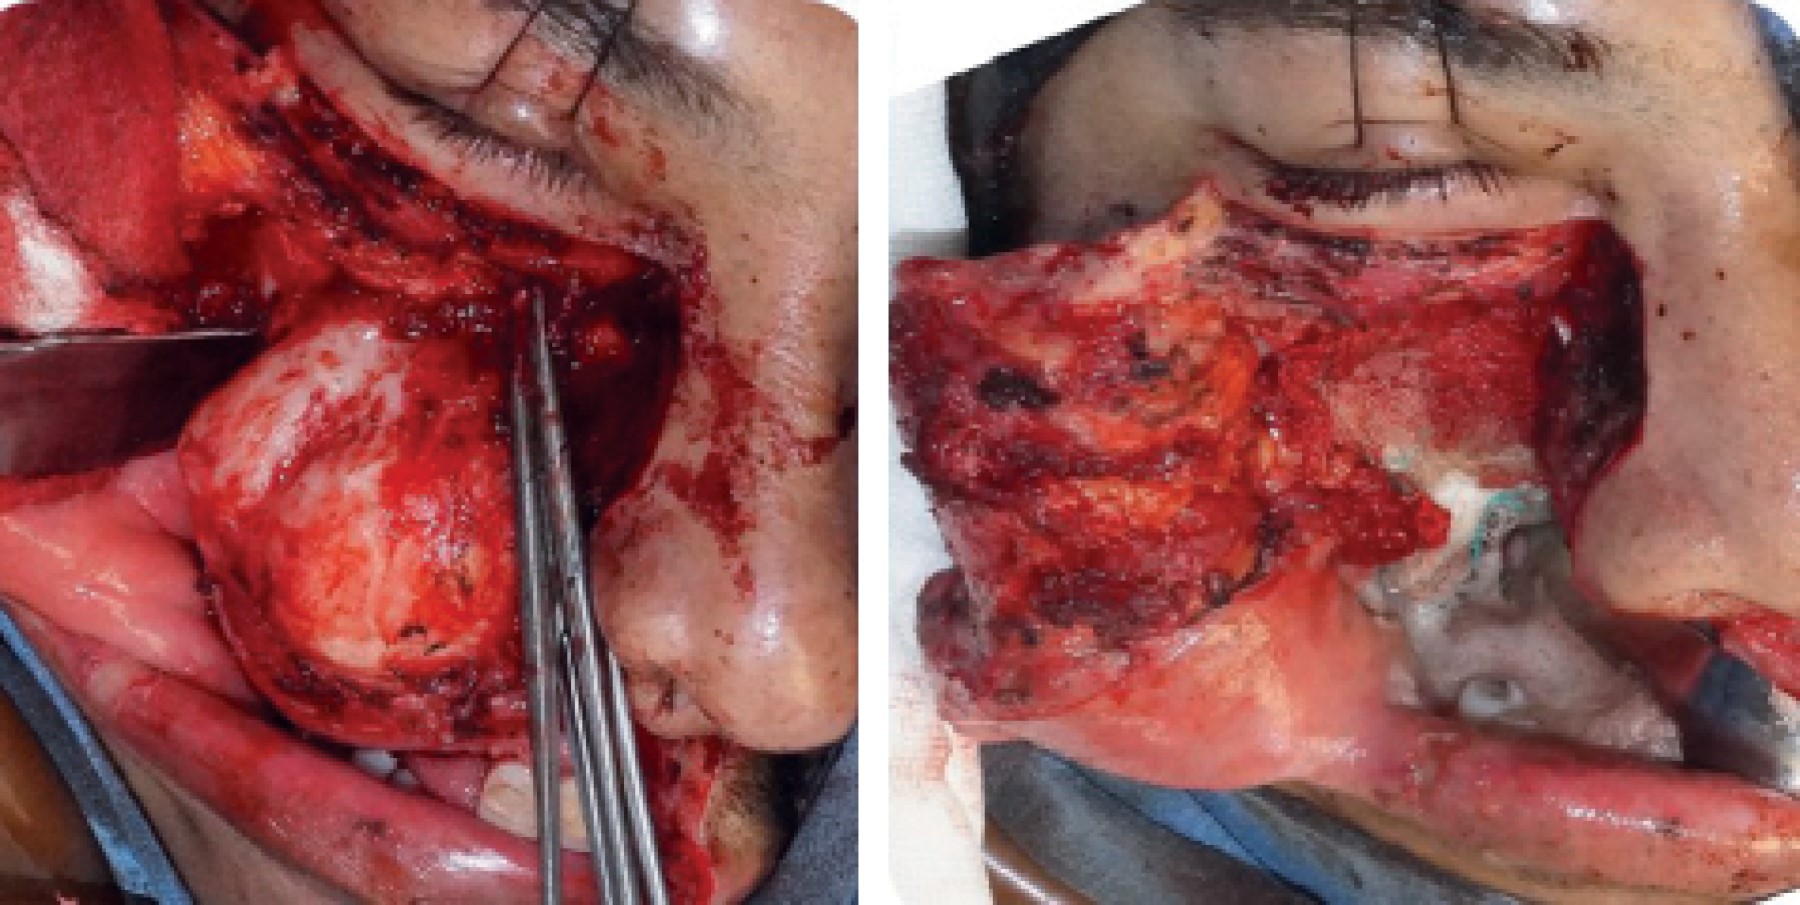

Odontogenic myxofibroma, case report with 5 years of follow-up.

Odontogenic myxoma is a slow-growing locally invasive intraosseous lesion with defined microscopic appearance. Radiographic appearance, is described as multilocular radiolucent lesion, which is reported in scientific literature as "honeycomb" or "soap bubbles" appearance most of the time; it exhibits dental displacement and cortical expansion. Histopathologically, stellate and spindle cells with cytoplasmic processes are observed in a mucoid or myxoid substance, with or without collagen; when it contains large amounts of mature cellular fibrous tissue, it is called myxofibroma. The present article presents the case of a 38 year old male, who attended the General Hospital in Uruapan, Michoacán due to an increased volume in the right maxillary region. Incisional biopsy was performed and the histopathological diagnosis of odontogenic myxofibroma was emitted. 33.6% of cases occur in the maxilla with a uniform distribution throughout the areas, and can erode the maxillary sinus. It has a recurrence rate of 10 to 33%, therefore ideal treatment is bloc resection leaving safety margins.

Figure 1

Figure 2

Figure 3

Figure 4